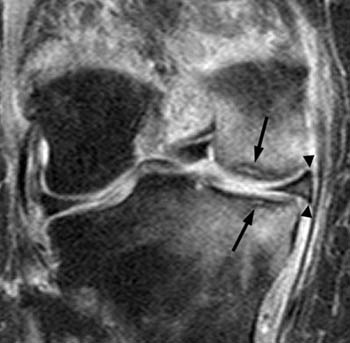

원반형 반월판(Discoid meniscus)이 인구의 3% 정도로 발생하는 흔한 변이에 해당하는데, 반월판의 형태학적인 거대화로 나타난다. (그림 46-7) 환자는 대개 무릎을 신전하고 굴곡할 때 염발음을 나타낸다. 이는 관상면 상에서 최적으로 진단되고 시상면 상에서는 그렇지 않은데, 기술상의 다양함이 나타날 수 있다. 대퇴외과의 중간 레벨을 관통한 관상면 MRI 영상에서 대퇴외과의 중간 포인트 아래로 가운데 부위로 이어지는 반월판이 원반형 반월판(discoid meniscus)으로 불린다.

△ 그림 46-7. 외측 원반형 반월판

중간 대퇴외과 레벨을 통과하는 관상면 T1 강조 시퀀스는 외측 원반형 반월판으로 나타나는 외측 반월판이 외측 대퇴외과의 중간 포인트 아래 가운데 부위로 연장됨을 보여준다. (화살표) 정상적인 내측 반월판은 내측 대퇴내과로 이어짐은 보이지 않는다. M = 내측, L = 외측